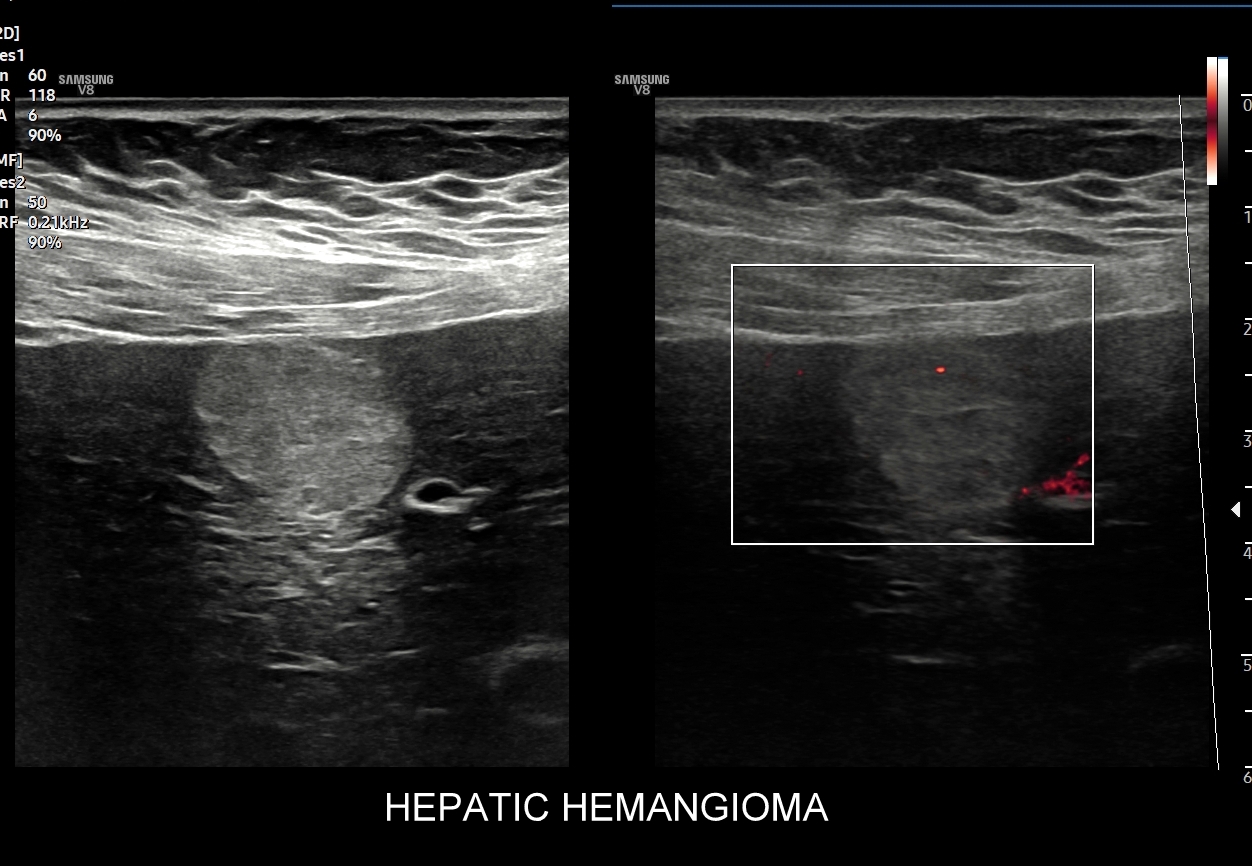

W badaniu USG w prezentacji B w niestłuszczonej wątrobie typowy naczyniak włośniczkowy lokalizuje się w pobliżu gałęzi żyły wątrobowej, a prezentuje się jako ostrookonturowana, hyperechogenna, jednorodna, krągła lub owalna zmiana ogniskowa. Ze względu na niską prędkość przepływu krwi i wynikające z tego ograniczenie detekcji w trybie color-Doppler w naczyniaku nie rejestruje się sygnału. Z kolei w trybie mikrounaczynienia (MVI / MVF) w zależności od czułości aparatury w naczyniaku można zaobserwować delikatny sygnał w postaci „poprószonego śniegu”.

W przypadku zarejestrowania w obrębie hyperechogennej zmiany ogniskowej wątroby w trybie kolorowego Dopplera lub Dopplera mocy (ang. power Doppler) drobnego naczynia lub naczyń, w szczególności krętych i o nieregularnym przebiegu, należy brać pod uwagę prawdopodobieństwo obecności złośliwej zmiany metastatycznej lub innego rodzaju zmiany ogniskowej.